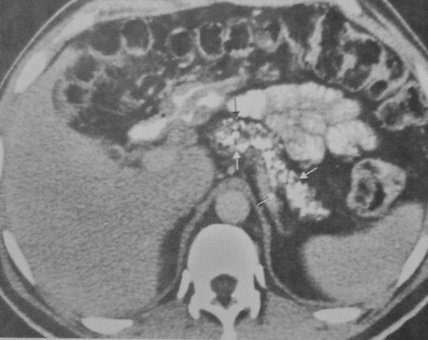

- Kontrastlı KT və ya MRT standart müayinədir, şişi və yayılma dərəcəsini müəyyənləşdirilməsində önəmlidir.

- Görüntüləmdə: erkən arterial fazada contrast tutan və venoz fazada yuyulan, MRT-də hipointens, ətraf toxumalara invaziv, böyüməyə meylli, baş nahiyyəsində yerləşərək xoledoxu və pankreatik axacağı genişləndirən (“iki axacaq simptomu”) törəmə